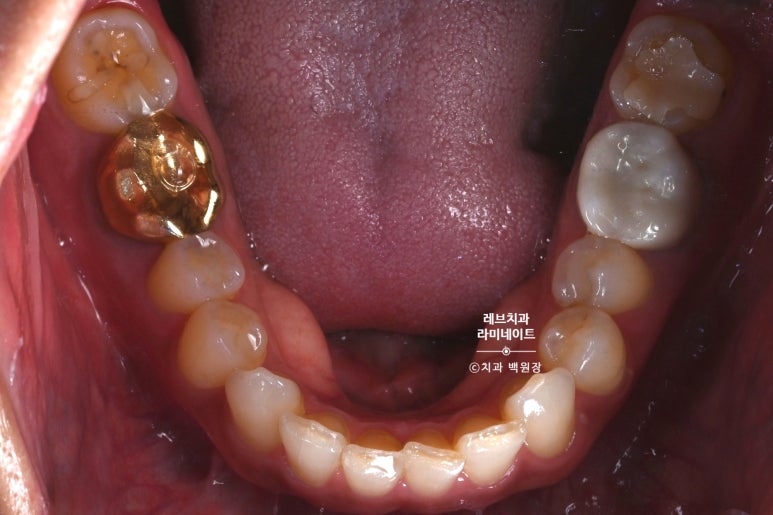

잇몸성형을 하면서, 치아를 다듬어주었습니다.

아래 앞니 레브네이트 베이직을 제작하기 위해 삭제된 치아의 모습입니다.

대부분의 치아가 무삭제 라미네이트를 할 수 있다고 홍보합니다.

치아를 하나도 안깎아도 되는 경우도 있지만, 애당초 치아를 깎아줘야 되는 상황도 분명 존재합니다.

이번 환자분 같은 경우, 위 아래 앞니가 매우 긴밀하게 그리고 깊게 물리는 상태셨어요.

이렇게 힘을 많이 받을 수 밖에 없는 상황인 경우, 아래 앞니 라미네이트 치료를 위한 치아 삭제는 필수입니다.

저희 강남 라미네이트 레브치과는 치아 삭제를 최소한으로 하기 위해 HASS 블록을 사용하고 있습니다.

라미네이트 블럭 중 가장 강한 강도를 갖는 블록에 속합니다.

다만, 색상이 단조로운 단점이 있어 특수한 컬러링으로 극복해내고 있습니다.

이 정도의 치아 삭제에 대해 어떻게 생각하실지 모르겠습니다만,

0.5mm 정도의 최소 치아 삭제를 한 모습입니다.

0.5mm 면... 도작 A4용지 5~10장 정도의 두께입니다. 정말 조금만 다듬는 기술!!!

자신감있게 얼마나 치아를 삭제하는지 보여드립니다.

레브치과는 환자분의 앞니를 지켜드립니다.